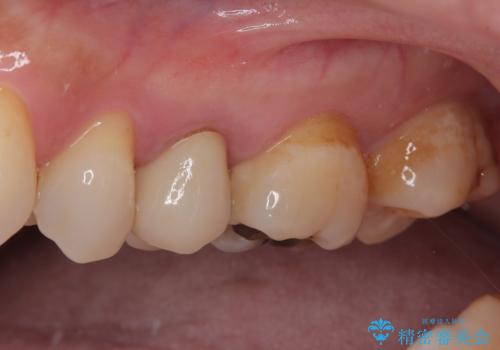

オールセラミッククラウンによる奥歯のむし歯治療

やはりむし歯は大きく、一部歯髄を切除することとなりましたが、その後は良好な経過をたどっています。